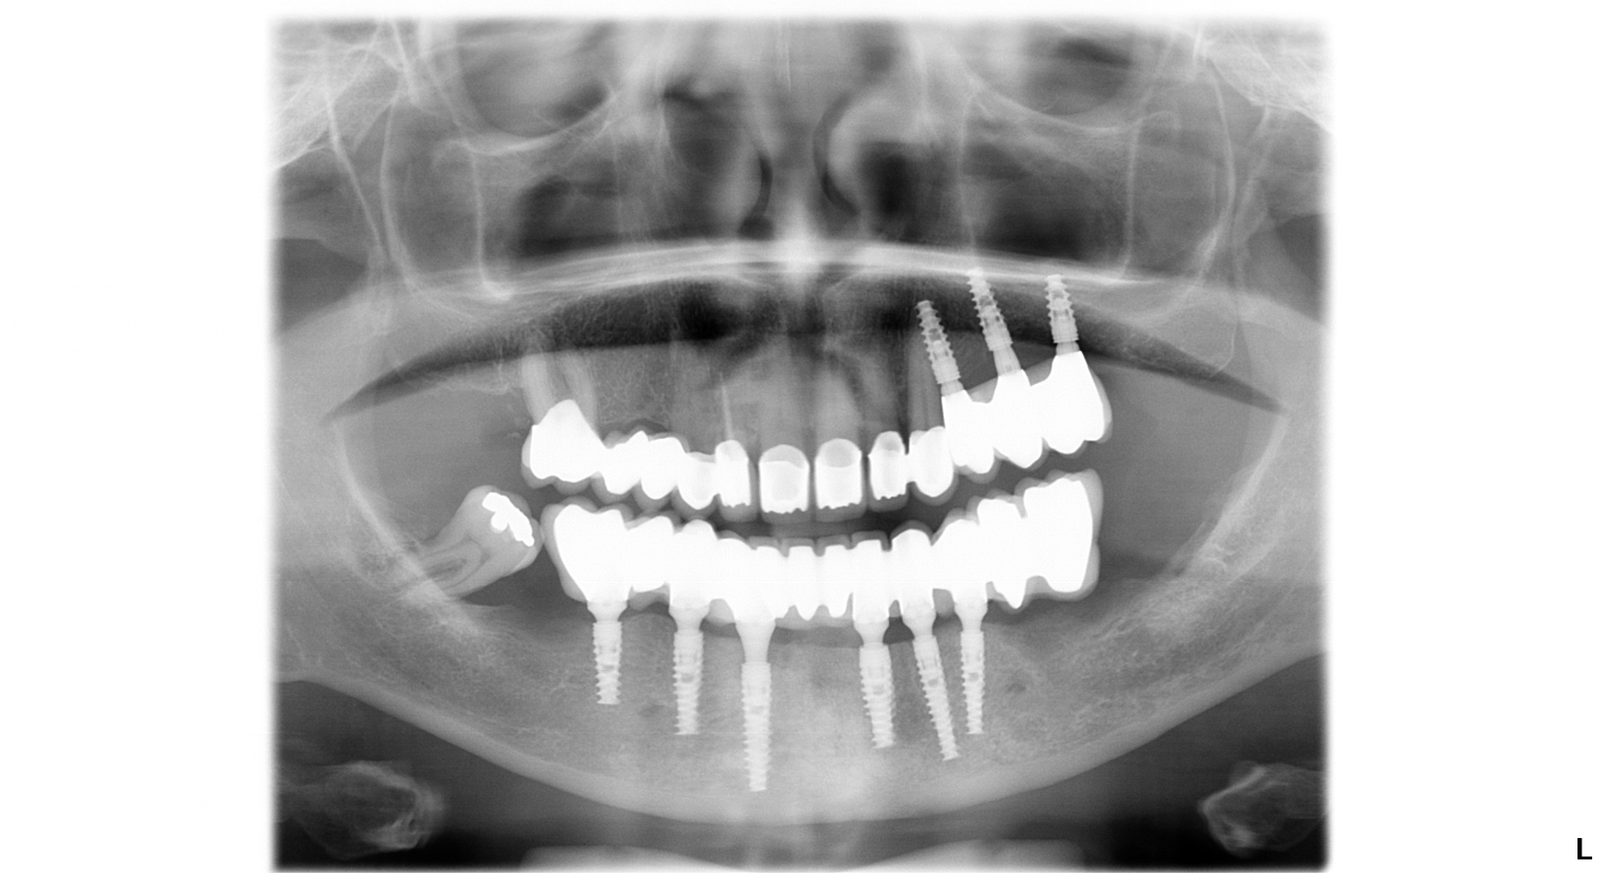

Po zahojení zubných implantátov, ktoré trvalo tri mesiace sa pacientka vrátila na kliniku a začalo sa s vrchnou čeľusťou. Pacientke bola urobená endodoncia – ošetrenie koreňového kanálika. Zuby sa obrúsili do požadovaného tvaru a pripravili sa na nasadenie koruniek. Nasledovalo odobratie odtlačkov zubných implantátov a obrúsených zubov. Výroba zubných  koruniek v zubnom laboratóriu trvala tri týždne. Posledná návšteva pacientky na klinike bola na nasadenie trvalých koruniek. Ponúkame Vám fotografie pacientky po ukončení ošetrenia a snímky pred a po ošetrení.

Snímok po ošetrení